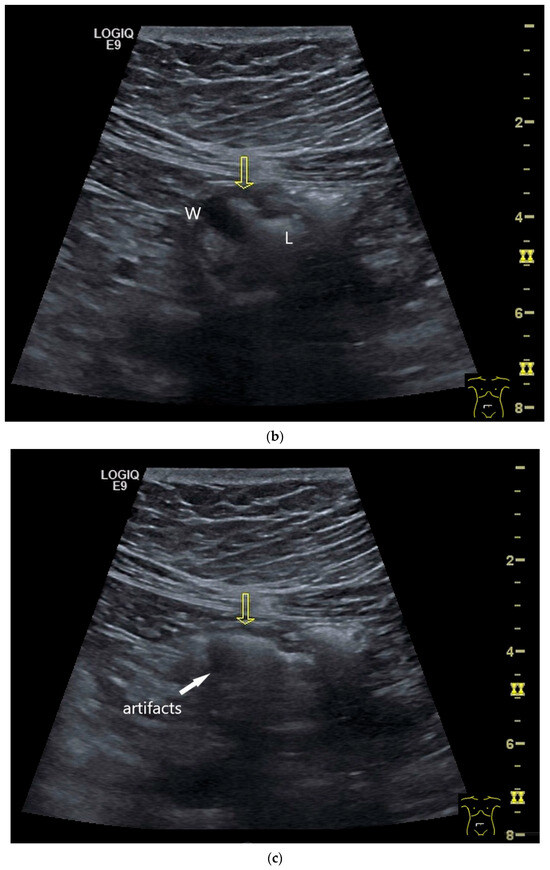

Figure 4.

NEN in the ileum: an approximately 14 mm hypoechoic nodular tumor is visible (a). Subsequently, peristalsis reveals a hypoechoic wall thickening (W) and hyperechoic luminal reflex (L) (b) and, finally, causes the tumor to be obscured by the luminal contents and dorsal artifacts (c). The region of the tumor is marked with a yellow arrow in all three images.